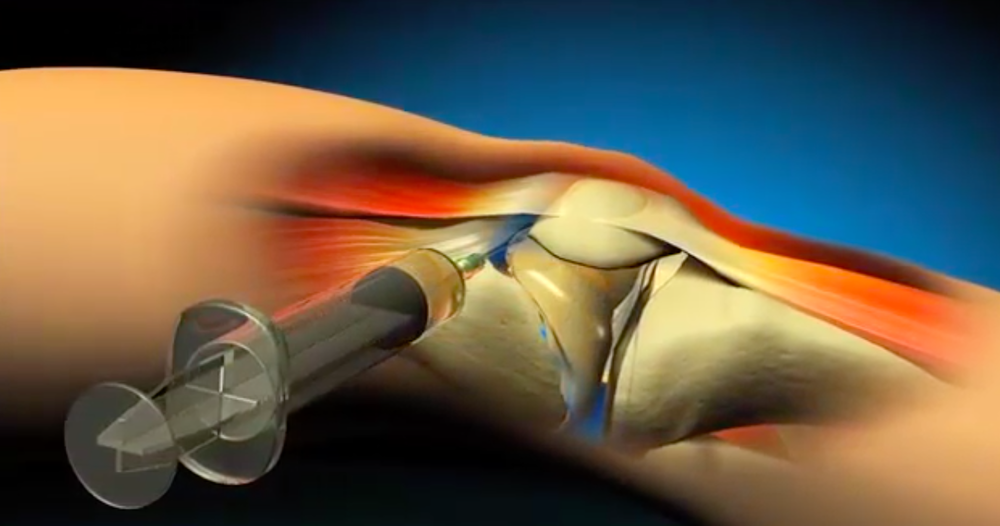

O procedimento é realizado em consultório por médico ORTOPEDISTA experiente, seguindo todos os padrões de assepsia e anti-sepsia, sendo feito geralmente 1 a 2 vezes por ano, conforme com cada caso. Muitas vezes precedido de punção articular do derrame (“água no joelho”).

Aplicação de uma injeção num local determinado do corpo; nesse caso numa articulação.

Geralmente para tratar pacientes com dores crônicas do joelho e diagnóstico de Artrose de Joelho ou Condropatia do joelho.

Anti-inflamatórios hormonais (como Betametasona e Triancinolona). Muitos usados em casos graves de artrose; associados ou não a Viscossuplementação.